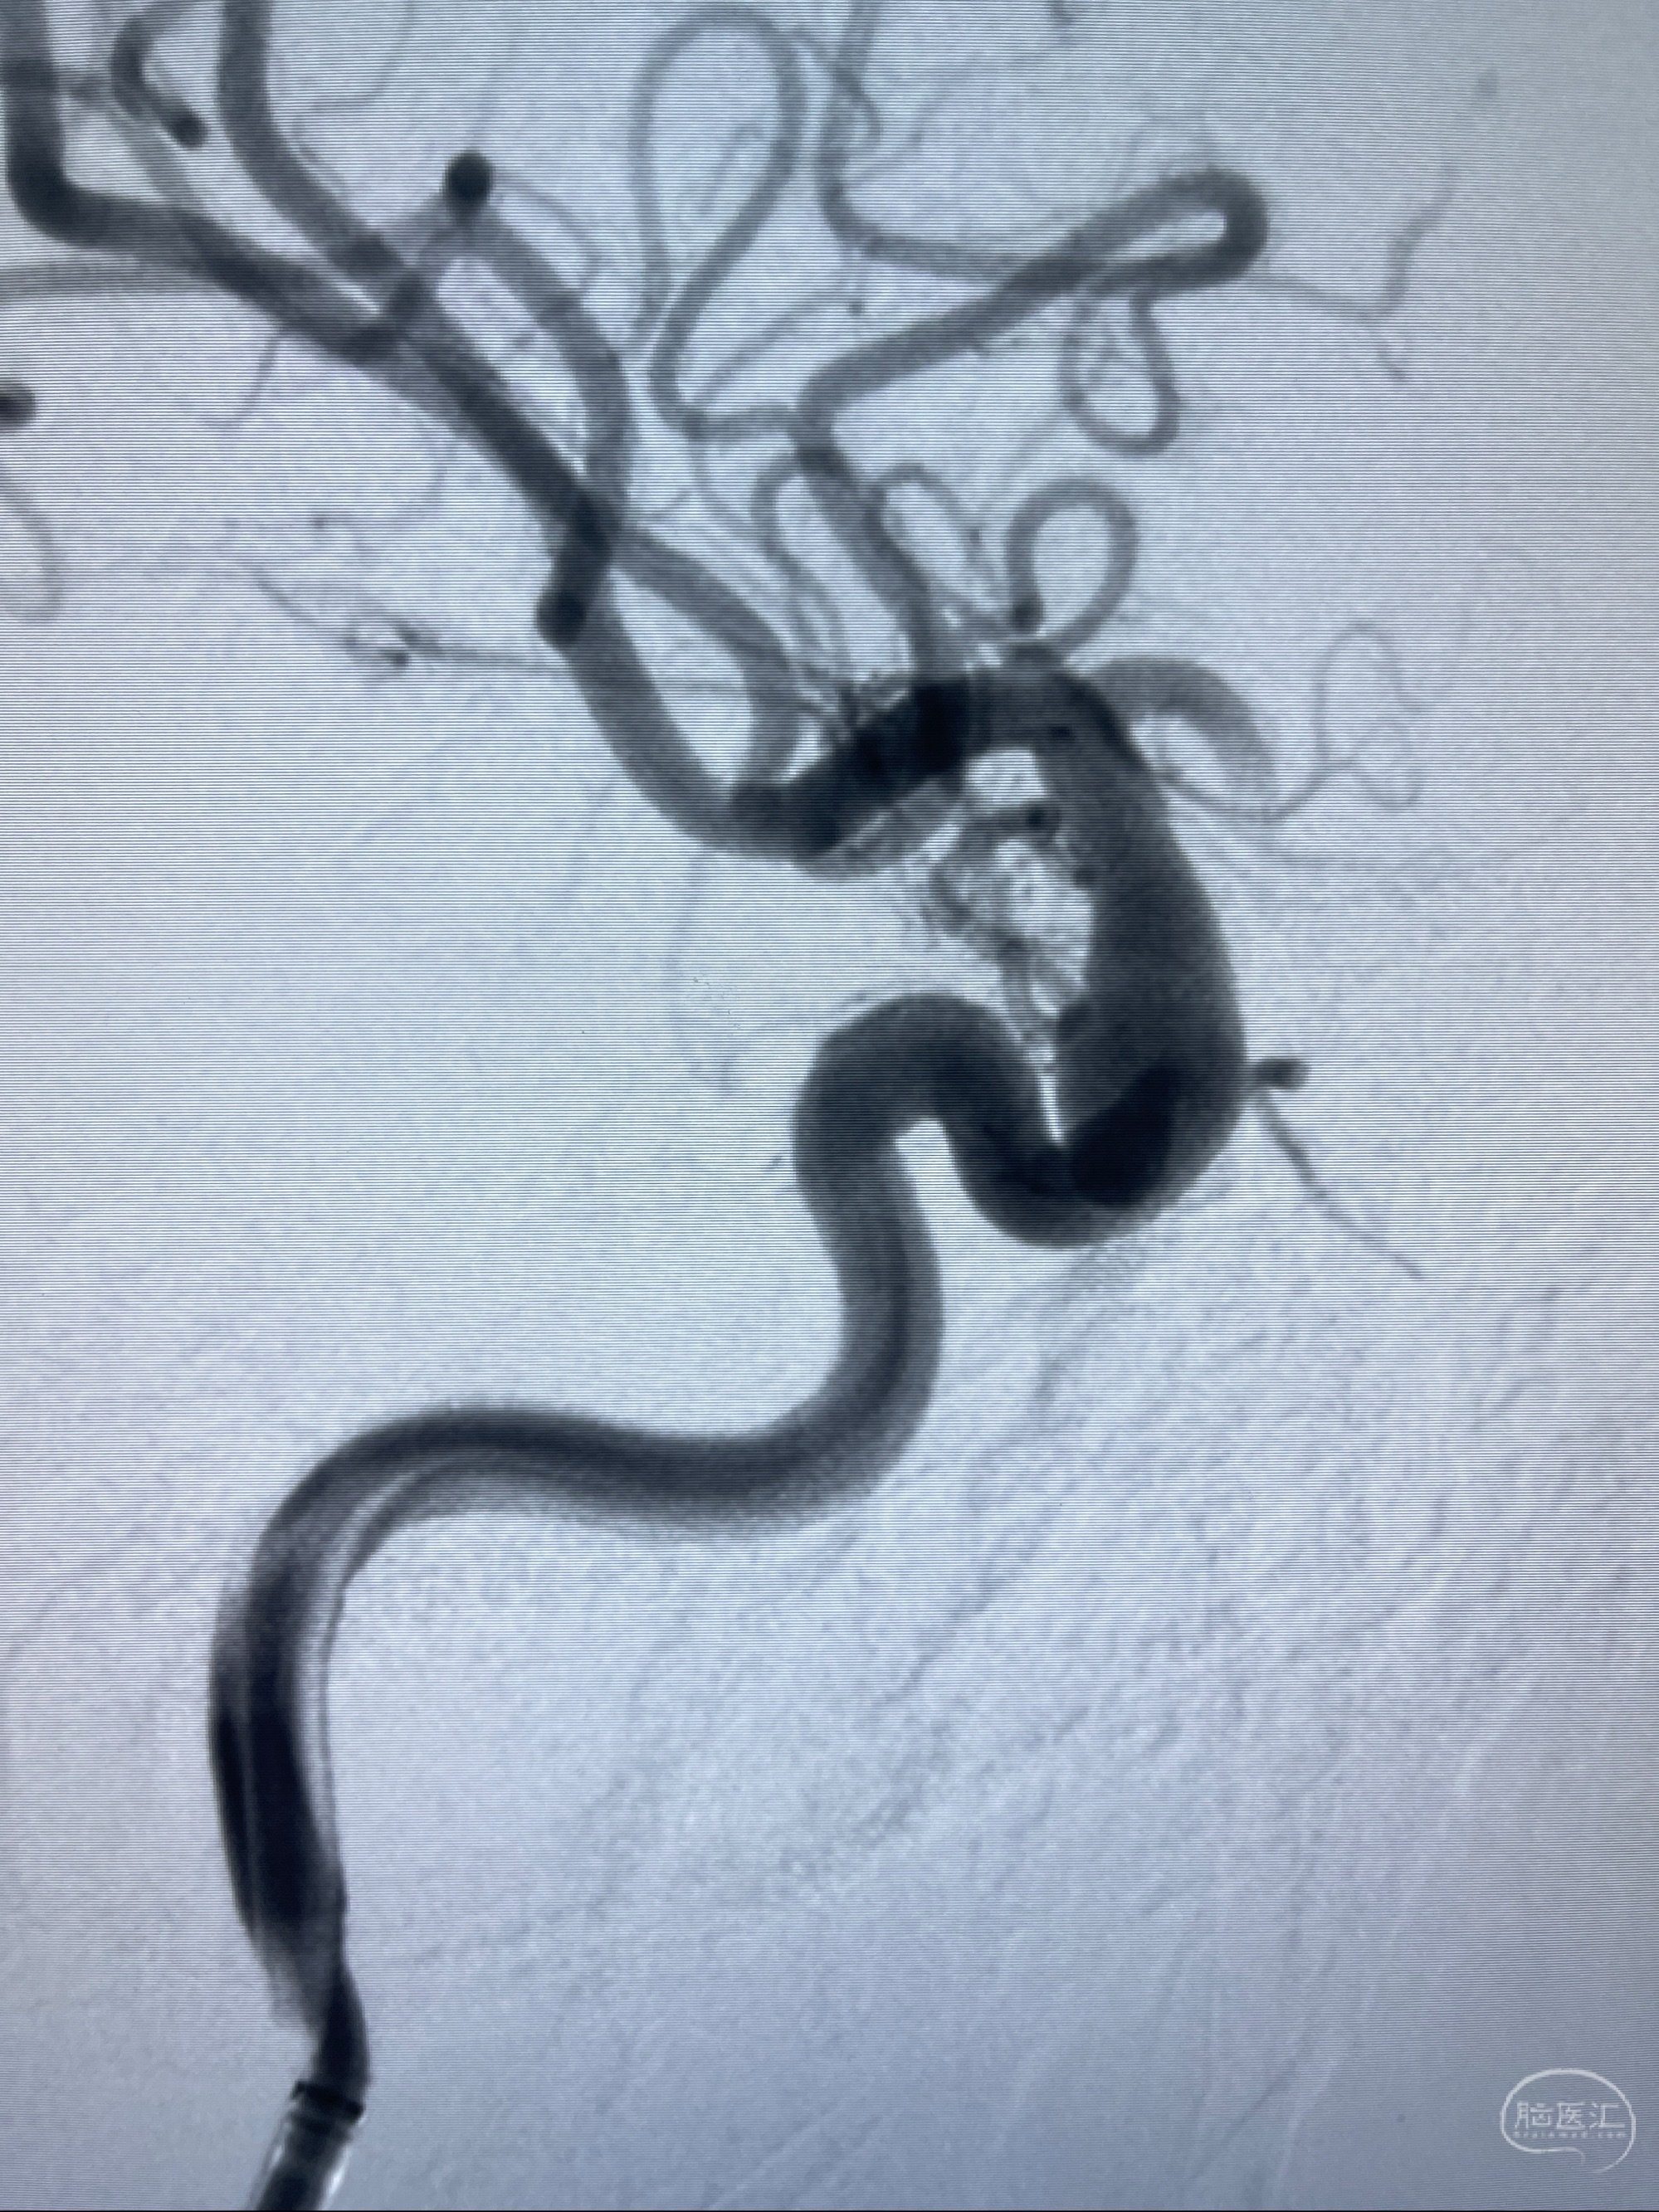

2023-08-01全麻下行双侧颈眼动脉瘤支架辅助栓塞

- pipeling4.5-20mm

- pipeline 4.0-20mm

手术顺利,麻醉苏醒佳,遵嘱动作

术后即刻CT